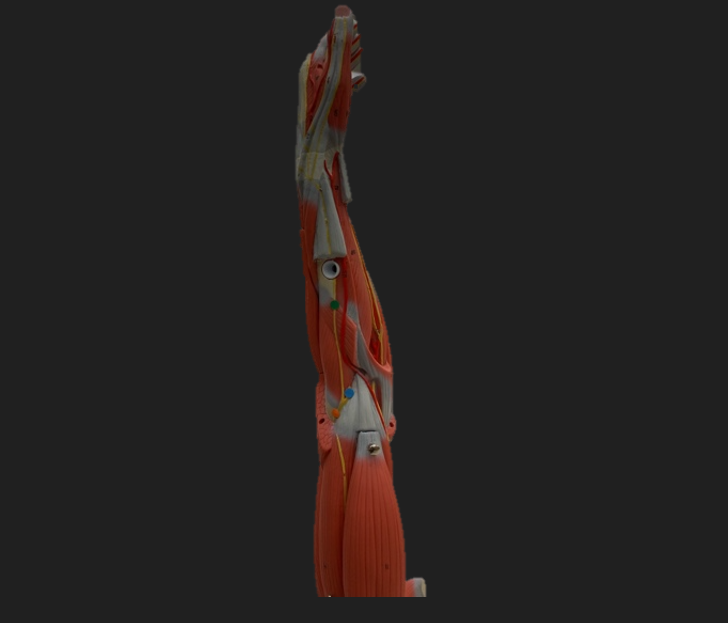

thoracodorsal n.

orange dot

axillary n.

pink dot

musculocutaneous n.

blue dot

median n.

green dot

ulnar n.

orange dot

radial n.

blue dot

deep branch of radial n.

green dot

superficial branch of radial n.